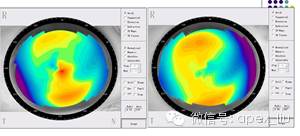

这是同一眼地形图,左图中的角膜中央红色高曲率部分,实际上是角膜表面的分泌物,瞬目后再做地形图,角膜中央红色高曲率部分消失。